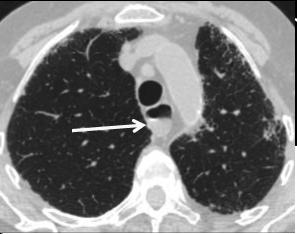

chaussette . Image TDM en fenetre parenchymateuse pulmonaire

,se donne des images si net de oesophage en coupe axiale ,

sagitale et de frontale ( voie image )

Mega oesophage : image radiologique

TDM fenetre parenchymateuse en coupe axiale |

Image Achalasia de oesophage en

coupe TDM sagitale |